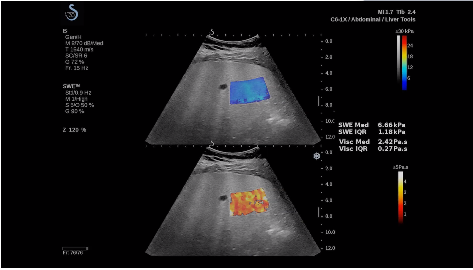

法國(guó)聲科影像(SuperSonic Imagine,SSI. Euroniex:FR0010526814)近日發(fā)表公告,宣布其研發(fā)的新一代“極速”超聲成像平臺(tái)(UltraFast Imaging),首次實(shí)現(xiàn)了肝臟的多項(xiàng)超聲定量評(píng)估新指標(biāo)同步檢測(cè),包括:Att PLUS,SSp PLUS和Vi PLUS等,基本涵蓋肝臟相關(guān)病理變化指征的如纖維化、脂肪變、炎癥等。據(jù)悉,此多項(xiàng)新技術(shù)新將搭載于新Aixplorer系列E超系統(tǒng)。

法國(guó)聲科影像公司(SuperSonic Imagine. SA,F(xiàn)rance),2005年由三位諾貝爾獎(jiǎng)級(jí)科學(xué)家主導(dǎo)創(chuàng)立,專注于E超的開(kāi)發(fā)和生產(chǎn),是目前世界上唯一可以同時(shí)應(yīng)用兩種波進(jìn)行人體檢測(cè)的系統(tǒng):縱波形成高質(zhì)量的二維組織結(jié)構(gòu)圖像,而橫波可以使醫(yī)生實(shí)時(shí)準(zhǔn)確地看到并分析組織的硬度,有效減少有創(chuàng)檢查、避免損傷。

E超相關(guān)技術(shù)已被多項(xiàng)多中心大樣本研究證實(shí)對(duì)于肝纖維化無(wú)創(chuàng)評(píng)估有重要意義,同時(shí)也可全面應(yīng)用于乳腺、甲狀腺、肝臟、前列腺、肌骨、婦科等全身各組織器官的定量評(píng)估和鑒別診斷。在慢性肝臟方面,聲科E超的肝臟相關(guān)定量診斷技術(shù)集,于2018年獲得美國(guó)FDA認(rèn)證,成為FDA歷史上首次獲批的單病種超聲全面定量解決方案。